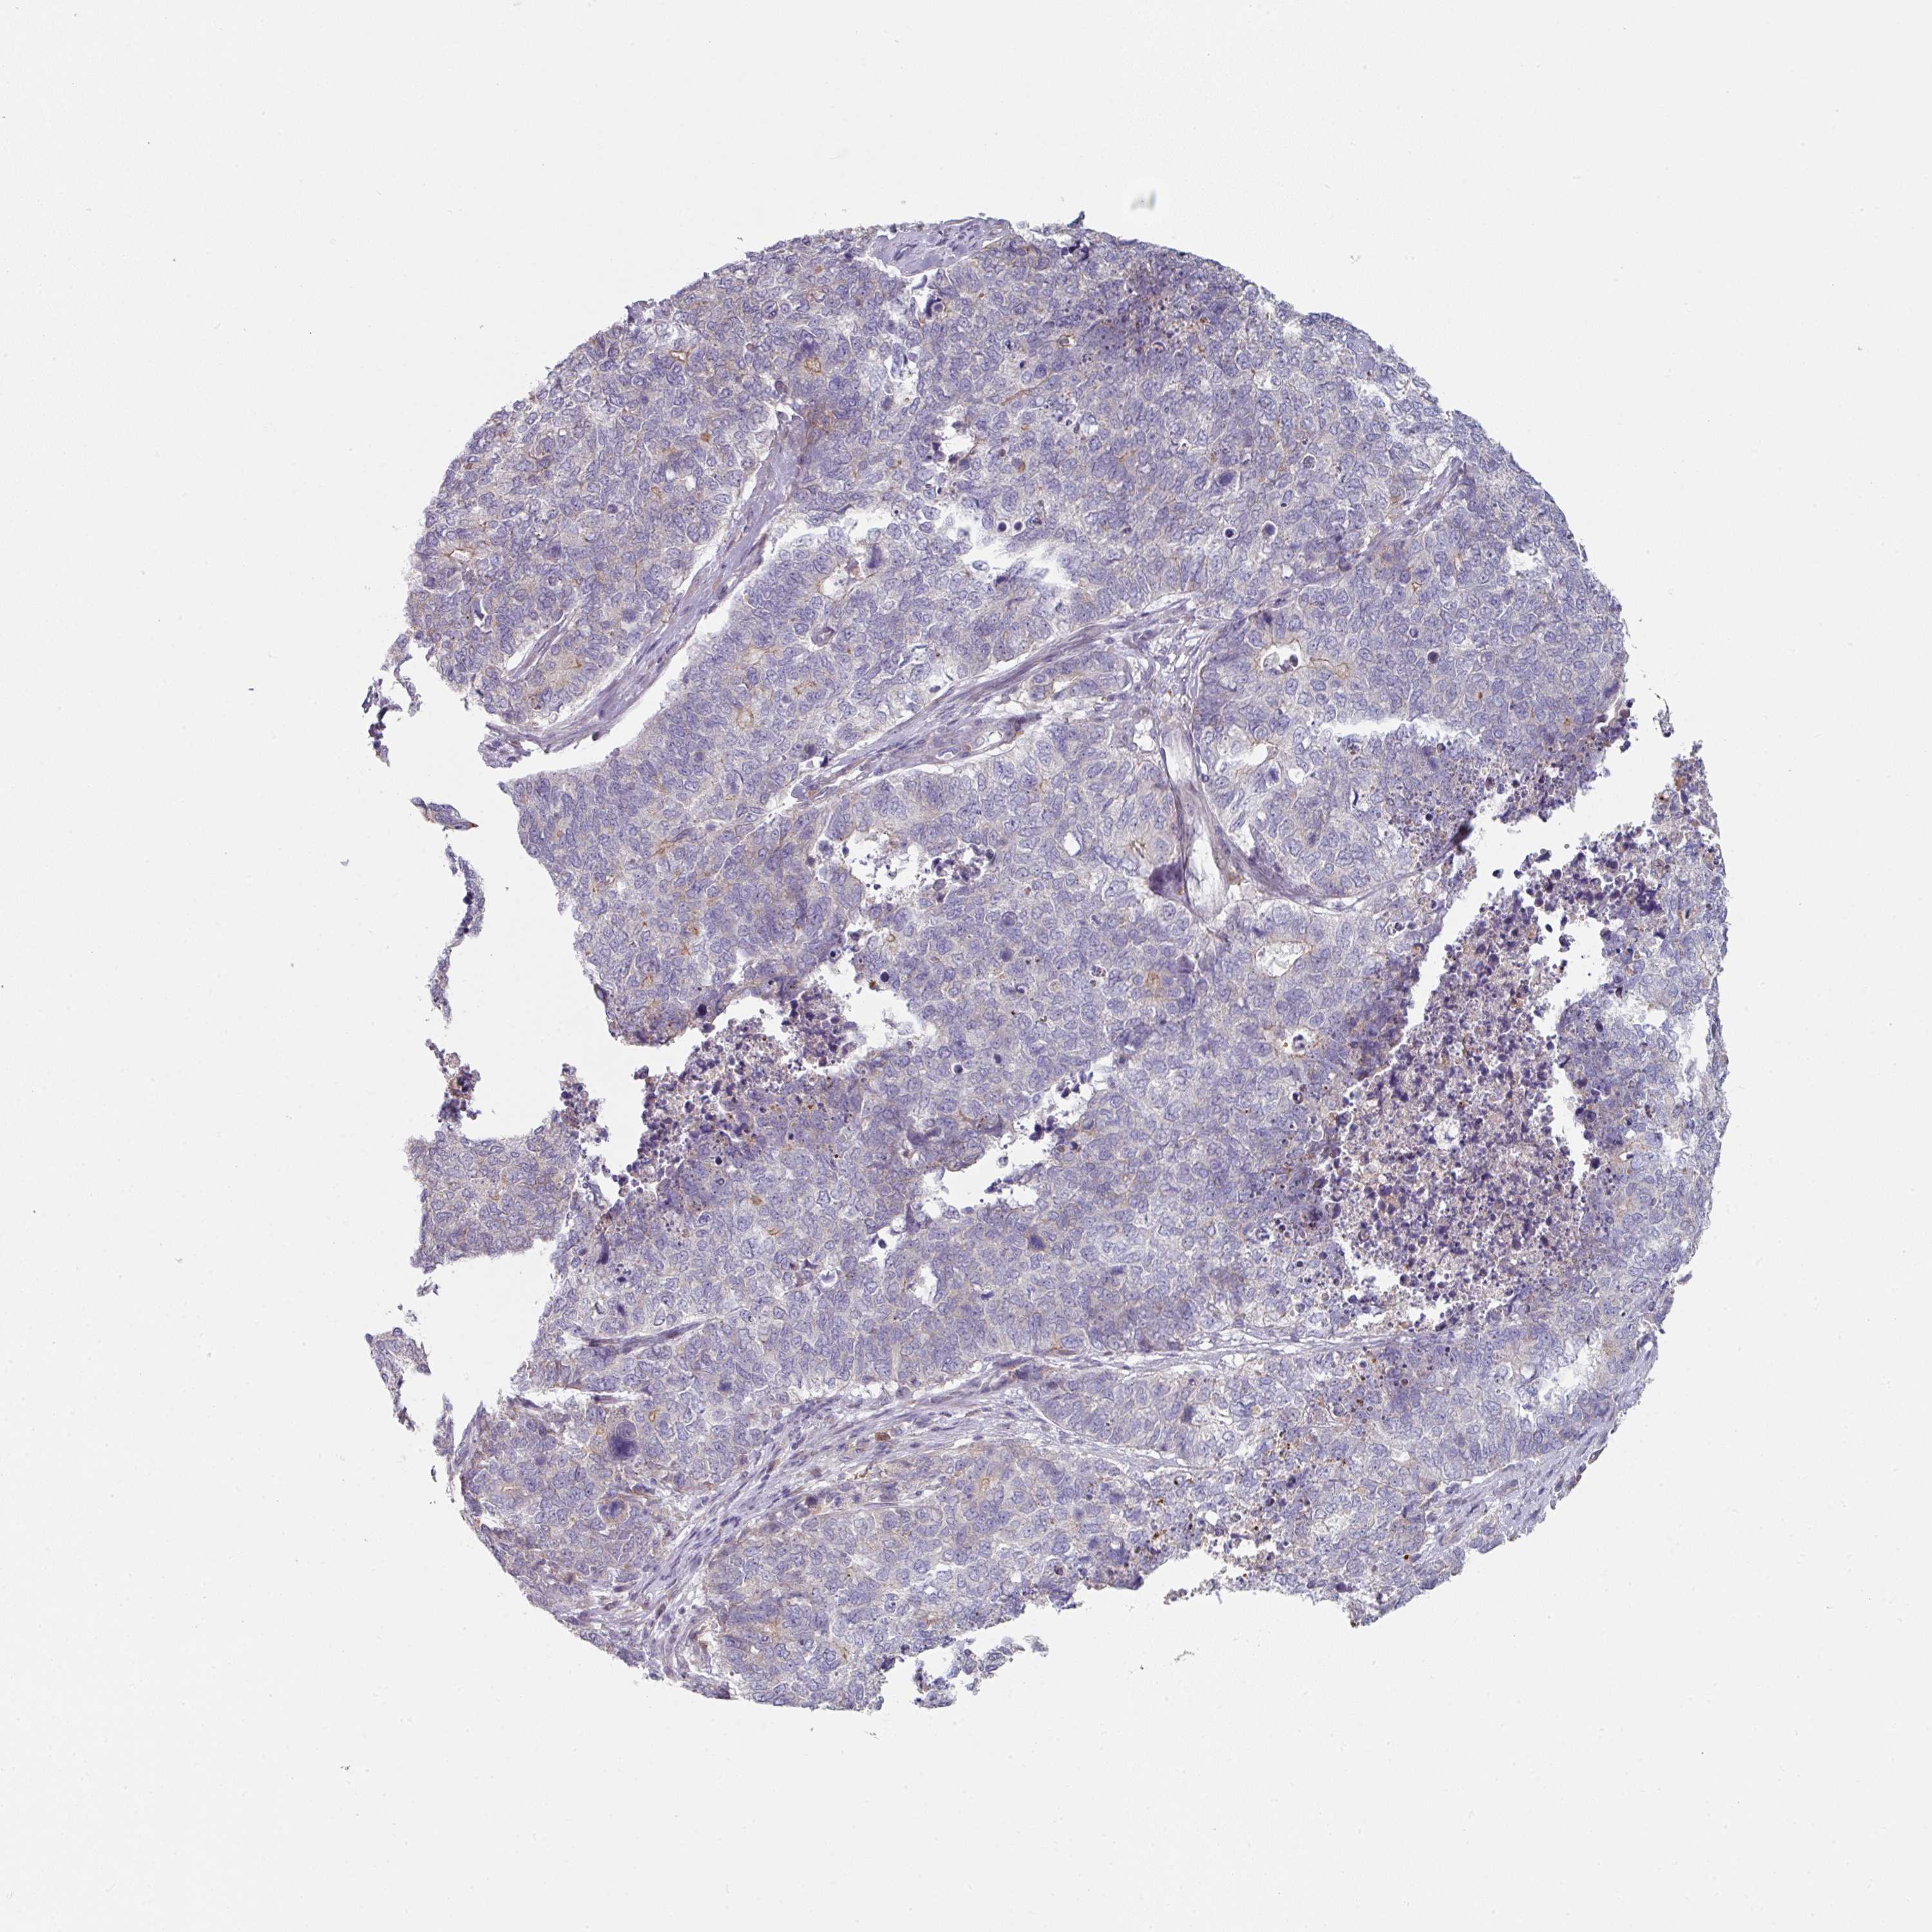

CERVICAL CANCER - Protein expressioni

A mouse-over function shows sample information and annotation data. Click on an image to view it in a full screen mode. Samples can be filtered based on level of antibody staining by selecting one or several of the following categories: high, medium, low and not detected. The assay and annotation is described here.

Note that samples used for immunohistochemistry by the Human Protein Atlas do not correspond to samples in the TCGA dataset.

Antibody stainingi

Antibody staining in the annotated cell types in the current human tissue is reported as not detected, low, medium, or high, based on conventional immunohistochemistry profiling in selected tissues. This score is based on the combination of the staining intensity and fraction of stained cells.

Each image is clickable and will lead to virtual microscopy that enables deeper exploration of all samples and also displays staining intensity scores, fraction scores and subcellular localization as well as patient and tissue information for each sample.

Antibody HPA052606

Antibody HPA077139

Staining

High

Medium

Low

Not detected

Intensity

Strong

Moderate

Weak

Negative

Quantity

>75%

75%-25%

<25%

None

Location

Nuclear

Cytoplasmic/membranous

Cytoplasmic/membranous,nuclear

Squamous cell carcinoma, NOS

Adenocarcinoma, NOS